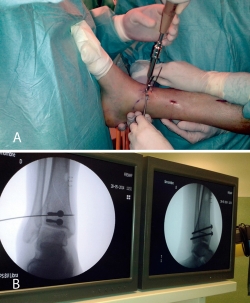

Realizamos los portales artroscópicos habituales en función de la situación de los extremos óseos de la fractura y practicamos un procedimiento idéntico al anterior: lavado, desbridamiento e identificación del foco de fractura (Figuras 12 a 16).

Figura 12. Caso 2: fractura espiroidea con afectación articular. Posicionamiento en férula de Braun. Tracción con vendas. Realización de portales.

Figura 13. Posteriormente, realizamos la limpieza del foco con cucharilla y la reducción del mismo mediante pinzas de cóndilo bajo control radioscópico/artroscópico, y fijación provisional con agujas de Kirschner.

Figura 14. A continuación, se realiza la medición y colocación secuencial de los tornillos.

Figura 15. Por último, se procede a la colocación definitiva de los tornillos.

Figura 16. Resultado final a los 4 meses.